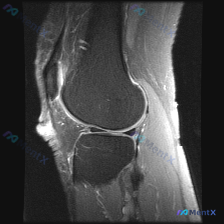

刚整理了一份膝关节MRI读片病例,分享一下完整分析思路。 病例影像基本信息 这是一张膝关节MRI矢状位图像,用户提问是否存在半月板异常,我们来一步步分析: 影像基础评估结果 1. 骨骼与关节: 股骨远端、胫骨近端皮质连续,无明显骨折,无明显骨髓水肿、软骨下囊肿,关节间隙和对合关系基本正常 2. 关节...